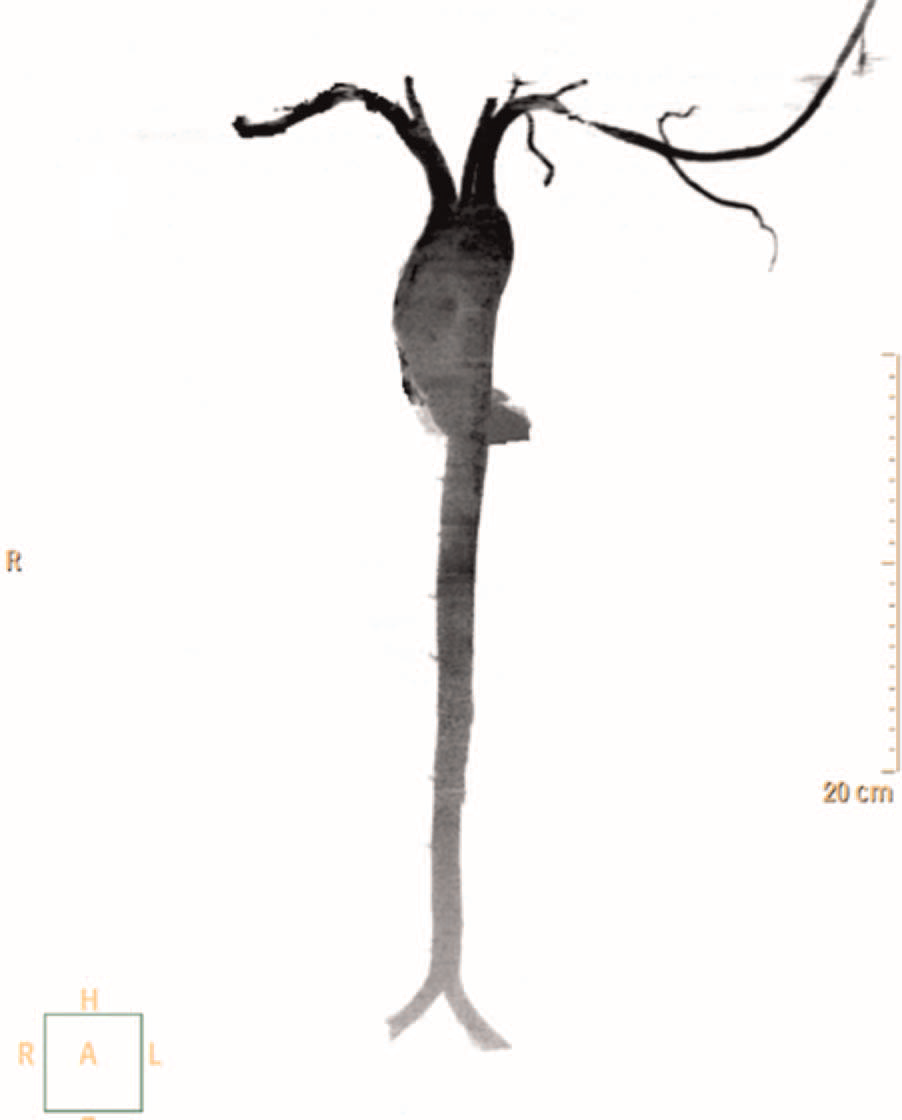

A 27-year-old man was referred for endovascular intervention to the left subclavian artery. There was no history of giddiness or claudication pain in the upper extremities. On examination, the left upper limb pulses were feeble. Blood pressure was 160/ 90 mm Hg in the right upper limb and 110/90 mm Hg in the left upper limb. There was a bruit in the left supraclavicular area. Routine blood investigations, including inflammatory markers, were normal. CT angiography revealed a discrete narrowing of the third part of the left subclavian artery (figure 1). A diagnosis of aorto-arteritis was considered, based on American College of Rheumatology criteria. However, there was no thickening of the vessel wall. The patient was re-evaluated. Wright’s hyperabduction test was performed.1 The signs disappeared with the arm in an adducted position and were reproduced in the abducted position. Repeat CT in the adducted position showed no evidence of subclavian obstruction (figure 2). A diagnosis of dynamically induced arterial thoracic outlet syndrome was made.

Figure 2 Repeat CT angiogram with the arm in the adducted position, revealing no evidence of subclavian artery obstruction.